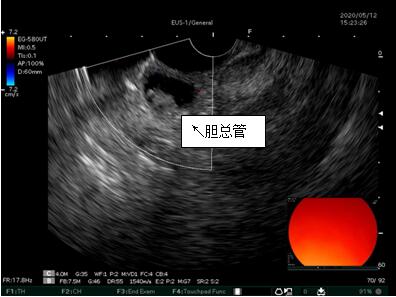

69歲王姓患者,因“發(fā)現(xiàn)無痛性黃疸1月”入院,根據(jù)患者病史,患者診斷傾向于壺腹部腫瘤所致梗阻性黃疸。予以完善腹部CT及上腹部MRI加MRCP均顯示肝內(nèi)外膽管擴(kuò)張,未發(fā)現(xiàn)明顯膽管,胰腺及十二指腸乳頭部腫瘤,且患者CA199正常。以前醫(yī)院未引進(jìn)超聲內(nèi)鏡,這類患者到此就遇到診斷瓶頸。此患者經(jīng)過消化內(nèi)科張丹霞副主任醫(yī)師完善超聲內(nèi)鏡檢查后,可以清楚顯示膽總管下段壁內(nèi)軟組織占位?;颊咄ㄟ^超聲內(nèi)鏡檢查診斷明確,轉(zhuǎn)至肝膽外科行手術(shù)治療。

超聲胃鏡圖片

膽總管小腫瘤性病變CT及MRI檢查陽性率偏低,因其低代謝特征,PET-CT陽性率也偏低,超聲內(nèi)鏡對這類疾病的診斷陽性率是所有檢查中最高的,且可行穿刺活檢進(jìn)一步確診病灶性質(zhì)。